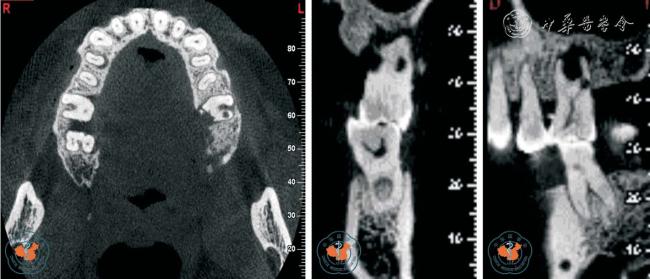

2. 观察牙根吸收情况:Tronstad12根据牙根吸收的起源部位将牙根吸收分为内吸收和外吸收,外吸收又根据不同临床表现分为炎症性外吸收、牙颈部外吸收和替代性外吸收。 早期牙根外吸收多无临床症状,X 线检查时才能发现。 由于根尖片只能显示相互重叠的二维影像,因此常不能清晰的显示吸收范围,难以准确评估牙根吸收的严重程度。 Estrela 等13报道指出根尖片识别牙根外吸收的假阴性率约为51.9%,假阳性率约为15.3%,尤其当病损位于颊侧或舌侧根面时,准确率更低。 而且,传统根尖片不能发现小于直径0.6 mm、深度0.3 mm的缺损。 CBCT 在很大程度上弥补了根尖片的缺点,其多层面重建(multiplannar reconstruction,MPR)技术可以显示病变的真实形态和部位,确定病变范围、破坏程度及周围牙槽骨的吸收状况,并可发现先前未发现的吸收缺损,有助于确定牙根吸收后的治疗规划,提高了患牙保存率(图3 ~4)。

图3 CBCT 轴位及MPR 重建显示上颌左、右第一磨牙牛牙症,其中左侧上颌第一磨牙根尖内吸收伴颊侧根折

图4 CBCT 轴位、VR、CPR 及MPR 重建冠、矢状位图像清晰显示根牙周病致牙根外吸收